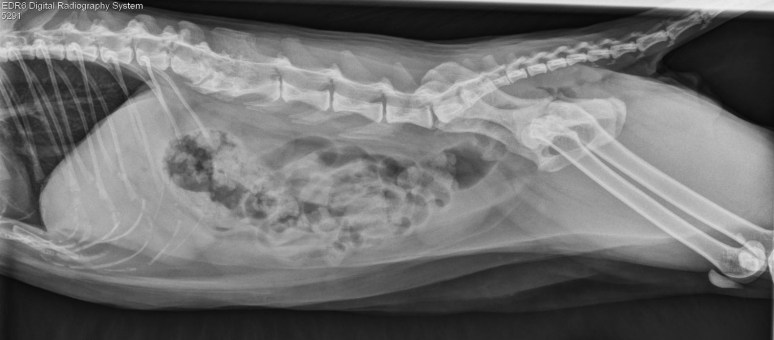

AJOUT à 19:30: Oh! non, Marc-André a trouvé un autre spectre… c’est donc une invasion en règle !

Cliquez ICI si vous n’avez pas trouvé ce second Poltergeist félin.